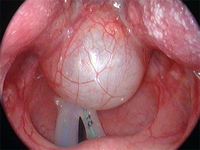

Vallecular cyst

From the personal teaching collection of Simone J. Boardman, MBBS, FRACS (OHNS) and C. Martin Bailey, BSc, FRCS, FRCSEd